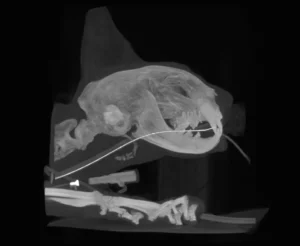

With this CT imaging system the entire head can be imaged in a single 18 second scan, allowing evaluation of teeth, jaw bones, maxillofacial anatomy, sinus and nasal cavities. CT images are composed of slices which allows millimeter by millimeter detailed assessment. In addition, a computer-generated three dimensional image may be produced. These images are superior to regular x-rays for evaluation of maxillofacial fractures, temporomandibular joint dislocations, and oral cancer.

Sample Images